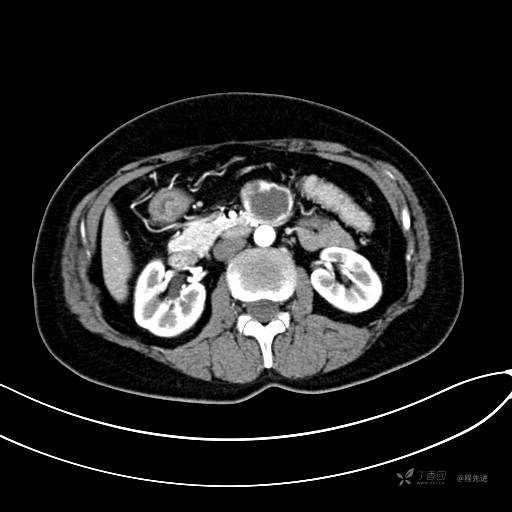

CT平扫